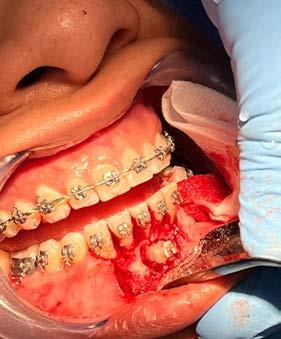

material de relleno del gap

Implante inmediato en sector estético con PRGF-ENDORET como único material de relleno del gap

implante hacia palatino para evitar la proximidad a la tabla vestibular implica que en muchos casos entre el implante y la tabla ósea vestibular se genere un espacio conocido como “gap” en el implante postextracción inmediata. Este espacio en ocasiones debe ser rellenado para evitar el colapso posterior estableciéndose como norma general que en aquellos casos en los que el grosor de la tabla vestibular oscile entre 1 y 2 mm y el espacio del gap es menor de 2 mm la capacidad regeneradora propia del alveolo haría que no fuese necesario el relleno del gap con ningún tipo de material para que se produjese la regeneración ósea en el mismo.13 Otros casos en los que la cortical sea de menor grosor o el gap de mayor distancia (o la combinación de ambos factores) debe ser rellenado el espacio con un biomaterial que permita la regeneración más favorable del defecto.13,14 Dentro de los materiales de relleno que pueden utilizarse, en la literatura internacional tenemos: hueso autólogo, hueso desmineralizado desecado y congelado, hueso mineralizado desecado y congelado, xenoinjerto, fosfato tricálcico y plasma rico en factores de crecimiento.15,16 El empleo de PRGF-Endoret para el manejo de este gap en el implante postextracción es un enfoque biológico y totalmente autólogo basado en las propias proteínas y señales celulares del paciente que nos garantiza buenos resultados a largo plazo, según las referencias publicadas en la literatura internacional donde se ha confirmado el potencial

que para estas situaciones altamente comprometidas es una excelente opción.18-24 En el presente caso clínico mostramos un paciente rehabilitado con un implante postextracción

inmediata y carga inmediata en el sector estético manejando el gap con la utilización exclusiva de PRGF-Endoret.

Caso clínico

Presentamos el caso de un paciente varón de 47 años, que acude a la consulta dental por presentar dolor, movilidad y fístula en la pieza dental 11. Este caso, fruto de un traumatismo previo, tuvo que ser endodonciado y posteriormente realizada sobre el mismo una apiceptomía, para abordar un quiste apical residual que no terminaba de evolucionar de forma favorable. El trabajado de rehabilitación posterior se llevó a cabo con una reconstrucción con poste y una carilla cerámica. Tras varios años, el diente ha comenzado de nuevo con los síntomas anteriormente descritos por lo que se sospecha la presencia de una fractura radicular. La

radiografía panorámica inicial para el diagnóstico nos aporta una imagen radiolucida entorno al ápice del diente en posición 11 ( Figura 1 ). Para conocer mejor el alcance de la lesión y las opciones terapéuticas de las que disponemos se lleva a cabo un cone-beam en el que se puede objetivar de forma precisa el defecto apical al diente. Este defecto es circunferencial y está dejando una reabsorción casi completa de la tabla ósea vestibular y parcial de la palatina, con un grosor de 1.9 mm, como vemos en el corte seccional (Figura 2). Si observamos la medida total en la zona media del incisivo dentral, necesitamos cubrir una anchura aproximada de 8 mm por lo que el implante que coloquemos irremediablemente dejará un gap, que según los protocolos quedará en vestibular. Utilizando una plataforma estándar de 4.1 mm el gap a rellenar será prácticamente de 4 mm según las medidas que nos

posible sobre los tejidos blandos y sobre el hueso remanente (Figura 5 y 6). Procedemos posteriormente a realizar una secuencia de fresado adaptada al lecho postextracción, alargando el alveolo con las fresas apicalmente y hacia palatino, donde se producirá el anclaje del implante. Con el lecho preparado colocamos el implante, quedándonos en vestibular el gap esperado de aproximadamente 4 mm como podemos ver en la

Figura 7. La utilización de un implante de longitud mayor y la inclinación hacia palatino nos permite lograr la estabilidad primaria necesaria para poder llevar a cabo una carga inmediata del implante. Una vez finalizada la inserción colocamos el transepitelial unitario para trabajar sobre el mismo generando la prótesis provisional de carga inmediata. Esta pieza intermedia (implante-prótesis) nos permite el uso de una interfase,

Una vez colocado el implante y el transepitelial para elaborar la prótesis de carga inmediata se realiza el sellado del gap vestibular, en este caso empleando únicamente PRGF-Endoret. El procedimiento es igual que

9 y 10. Relleno del gap con PRGFEndoret, situando un coágulo recién activado de la fracción 2 en el fondo del alveolo y posteriormente un tapón de fibrina para la zona más superior (fracción 1 activada y retraída).

para el sellado de un alveolo postextracción, colocándose un coágulo de PRGF-Endoret recién activado de la fracción 2 (con alta liberación de factores de crecimiento) y sobre el mismo un tapón de fibrina autóloga sellando la zona más cercana al reborde alveolar (Figura 9 y 10). No se utilizan puntos de sutura para evitar el colapso del tejido blando del alveolo, además que por la adhesividad de la fibrina se mantiene en